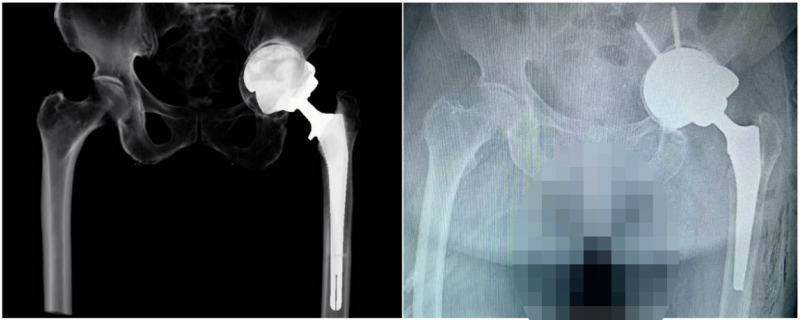

image009.png

图中所示人工智能术前规划和测量软件模拟的术后X线片与真实的术后X线片相一致。